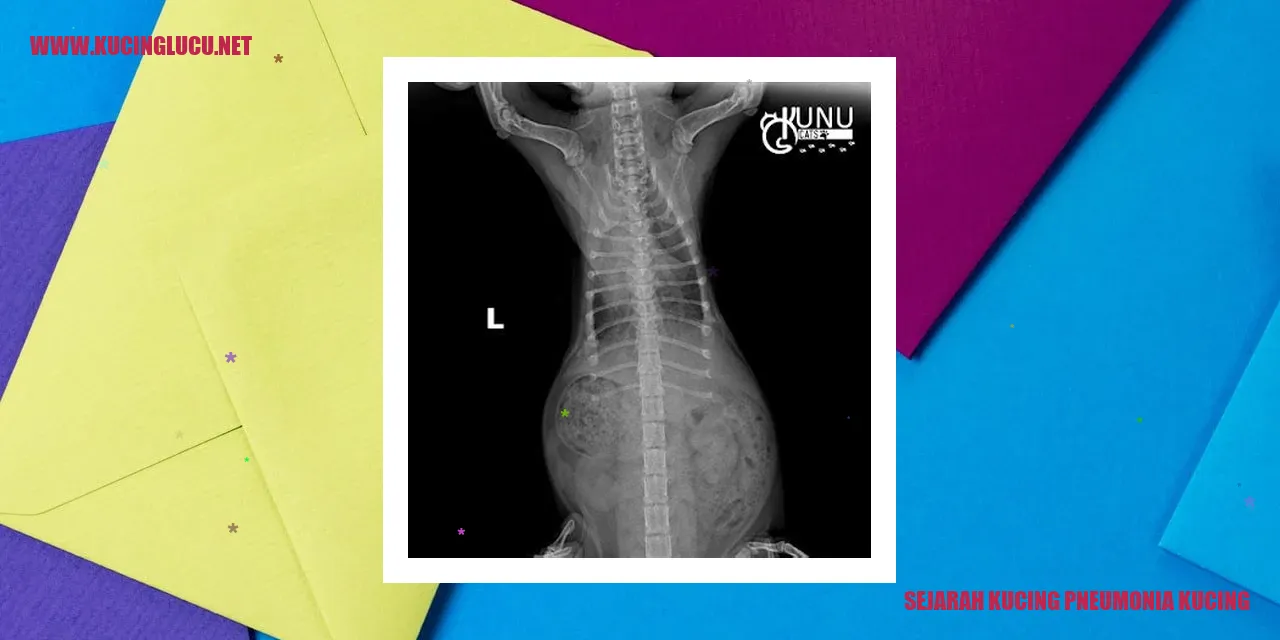

Penjelasan dan Tanda-tanda Kucing Terkena Pneumonia

Kondisi penyakit pernapasan pada kucing yang disebabkan oleh infeksi pada saluran pernafasan bagian bawah disebut pneumonia. Gejala utama kucing yang mengalami pneumonia biasanya meliputi batuk, kesulitan bernapas, napas yang sangat cepat atau terengah-engah, dan penurunan nafsu makan. Pneumonia pada kucing terjadi akibat infeksi bakteri, virus, ataupun jamur.